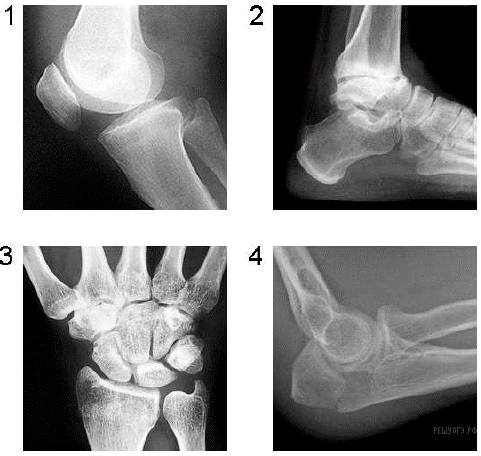

На рисунках представлены рентгенограммы суставов человека. Какой цифрой отмечена рентгенограмма лучезапястного сустава?

Ответ: